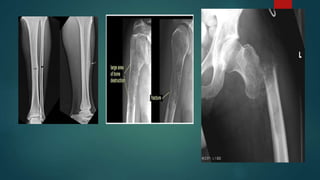

d. Comminuted fracture:

 Fracture with multiple fragments

 Caused by a compression or crushing force along the long axis of the bone

 X- ray: more than two fragments; unstable

e. Segmental fracture:

 Two fractures in one bone

 But at different level

ON THE BASISOF PATTERN 1. Complete fracture:  Bone is split into two or more fragments a. Transverse fracture:  Fracture line is perpendicular to the long axis of the bone  Caused by a tapping or bending force  X- ray: fragments usually remains in place after reduction b. Oblique fracture:  Fracture line is oblique  Caused by a bending force

 Has acomponent along the long axis of the bone  X- ray: tend to shorten and re- displace even if the bone is splinted c. Spiral fracture:  Fracture line runs spirally in more than one plane  Caused by a primarily twisting force  X- ray: same as oblique fracture d. Comminuted fracture:  Fracture with multiple fragments  Caused by a compression or crushing force along the long axis of the bone  X- ray: more than two fragments; unstable

e. Segmental fracture: Two fractures in one bone  But at different level 2. Incomplete fracture:  Bone is incompletely divided  Periosteum remains in continuity  Example: greenstick fracture:  Bone is buckled or bent  Seen in children  Bone is more springy than adults